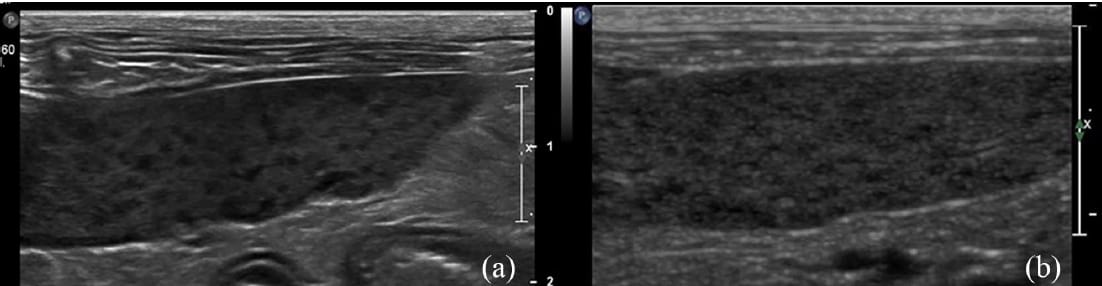

Ultrasonographic images of two feline spleens showing a honeycomb pattern with multiple small hypoechoic foci with

a final diagnosis of (a) pyogranulomatous splenitis and (b) lymphoid hyperplasia